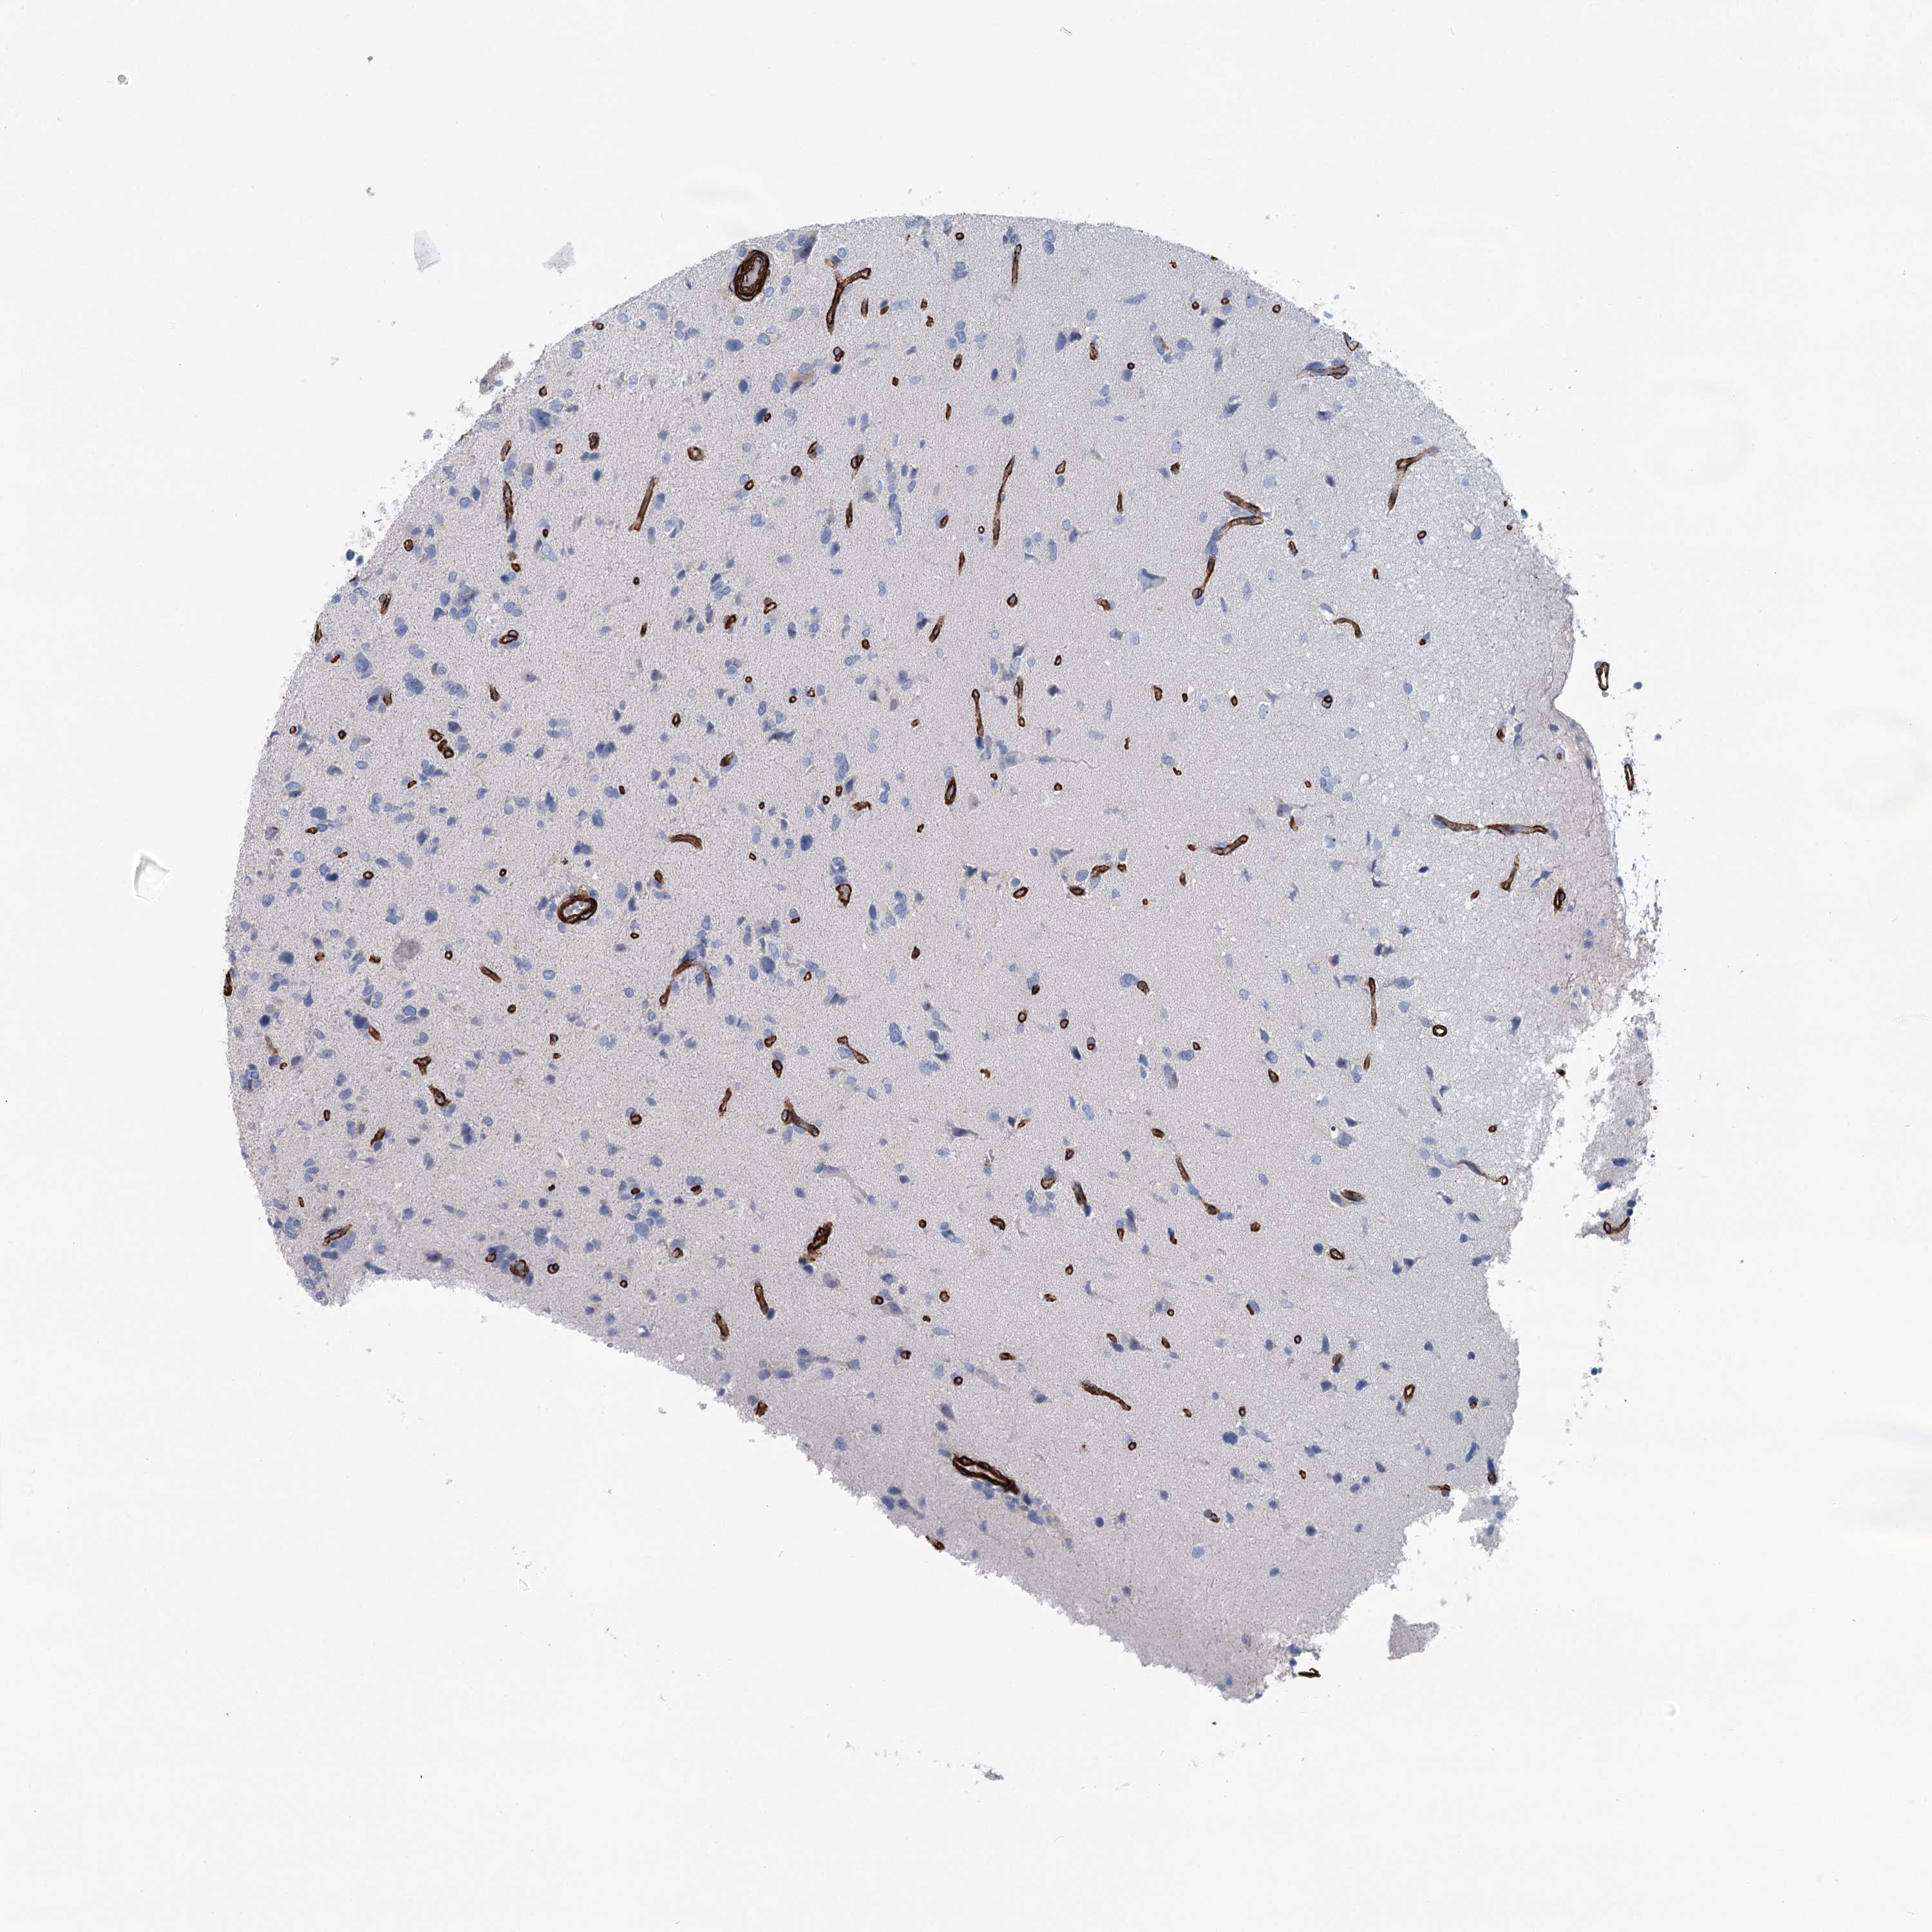

GLIOMA - Protein expressioni

A mouse-over function shows sample information and annotation data. Click on an image to view it in a full screen mode. Samples can be filtered based on level of antibody staining by selecting one or several of the following categories: high, medium, low and not detected. The assay and annotation is described here.

Note that samples used for immunohistochemistry by the Human Protein Atlas do not correspond to samples in the TCGA dataset.

Antibody stainingi

Antibody staining in the annotated cell types in the current human tissue is reported as not detected, low, medium, or high, based on conventional immunohistochemistry profiling in selected tissues. This score is based on the combination of the staining intensity and fraction of stained cells.

Each image is clickable and will lead to virtual microscopy that enables deeper exploration of all samples and also displays staining intensity scores, fraction scores and subcellular localization as well as patient and tissue information for each sample.

Antibody HPA038143

Antibody HPA038144

Staining

High

Medium

Low

Not detected

Intensity

Strong

Moderate

Weak

Negative

Quantity

>75%

75%-25%

<25%

None

Location

Nuclear

Cytoplasmic/membranous

Cytoplasmic/membranous,nuclear

Glioma, malignant, High grade

Glioma, malignant, Low grade

Glioblastoma, NOS